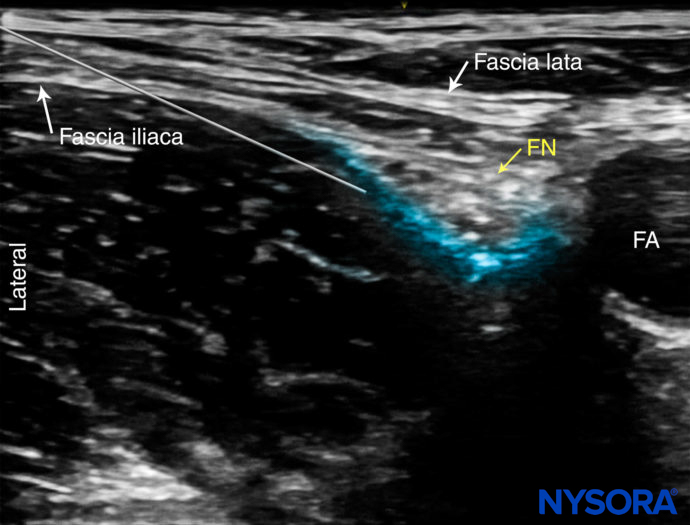

With the patient in the supine position, the skin over the femoral crease is disinfected and the transducer is positioned to identify the femoral artery and nerve. If the nerve is not immediately apparent lateral to the artery, tilting the transducer proximally or distally often helps to image and highlight the nerve from the iliacus muscle and the more superficial adipose tissue. In doing so, an effort should be made to identify the iliacus muscle and its fascia, as well as the fascia lata, because injection underneath a wrong fascial sheath may result in nerve block failure. Once the femoral nerve is identified, a skin wheal of local anesthetic is made 1 cm away from the lateral edge of the transducer. The needle is inserted in-plane in a lateral to medial orientation and advanced toward the femoral nerve (Figure 5).

If nerve stimulation is used (0.5 mA, 0.1 msec), the passage of the needle through the fascia iliaca and contact of the needle tip with the femoral nerve usually is associated with a motor response of the quadriceps muscle group. In addition, a needle passage through the fascia iliaca is often felt. Once the needle tip is adjacent (either above, below, or lateral) to the nerve (Figure 6), and after careful aspiration, 1–2 mL of local anesthetic is injected to confirm proper needle placement (Figures 7 and 8). Proper injection will push the femoral nerve away from the injection.

FIGURE 2. (A) Cross-sectional anatomy of the femoral nerve (FN) at the level of the femoral crease. The FN is seen on the surface of the iliopsoas muscle covered by fascia iliaca (white arrows). The femoral artery (FA) and femoral vein (FV) are seen enveloped within their own vascular fascial sheath created by one of the layers of fascia lata. (B) Sonoanatomy of the FN at the femoral triangle.

FIGURE 6. Ultrasound image of the needle path to nerve block the femoral nerve. The needle pierces the fascia iliaca lateral to the femoral nerve (FN) and the needle tip is advanced along the deep border of the nerve. FA, femoral artery.

FIGURE 7. Simulated needle path and spread of local anesthetic (blue-shaded area) to nerve block the femoral nerve (FN). FA, femoral artery.